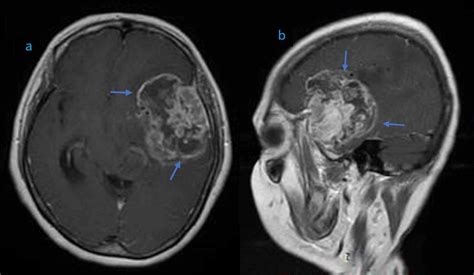

The journey toward a formal diagnosis usually begins with a neurological examination followed by advanced imaging. Physicians rely on several diagnostic tools to map the tumor’s size, location, and relationship to vital brain structures. Magnetic Resonance Imaging (MRI) with contrast remains the gold standard for visualizing these growths. In many cases, specialized sequences such as spectroscopy or perfusion imaging are used to differentiate between tumor tissue and postoperative changes.

• high grade glioma MRI